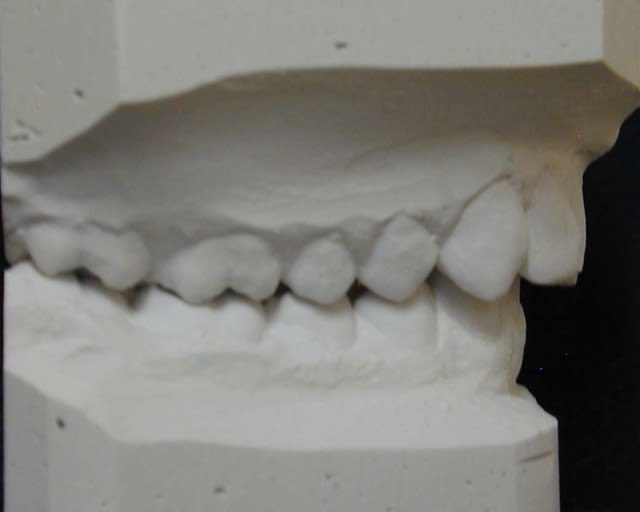

cas 2;Lea

BHG 9mois PUIS eln +2 LBs 15mois

l'occlusion;

NB: Dans les 2 cas , pas de version des inc infs!